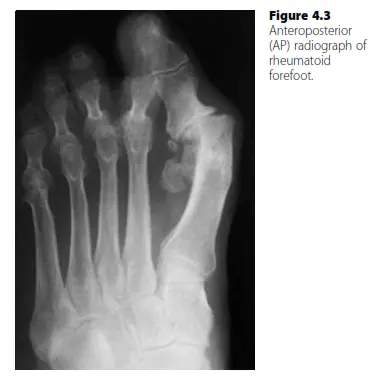

- الأشعة السينية (X-rays): تُعد الأشعة السينية أساسية لتقييم:

- تضييق المسافات المفصلية وتآكل العظام (Erosions).

- خلع المفاصل المشطية السلامية وتشوهات الأصابع.

- انهيار قوس القدم (القدم المسطحة) وتشوهات القدم الخلفية.

- زوايا القدم (مثل الزاوية بين الأمشاط) لتقييم تباعد مقدمة القدم.